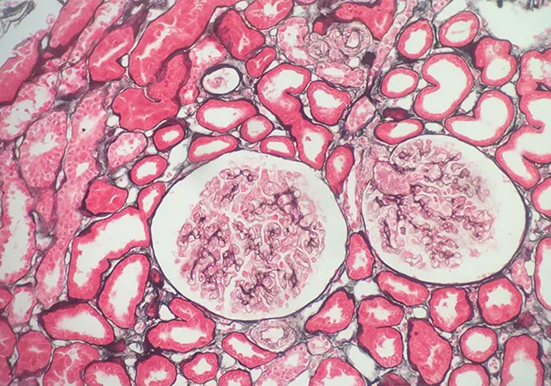

刚果红染色

刚果红染色是一种常用的生物染色方法,以下是关于它的详细介绍:基本信息染料性质:刚果红是一种经典的酸性染料,化学式为 C32H22N6Na2O6S2,是一种棕红色粉末,能溶于水和···